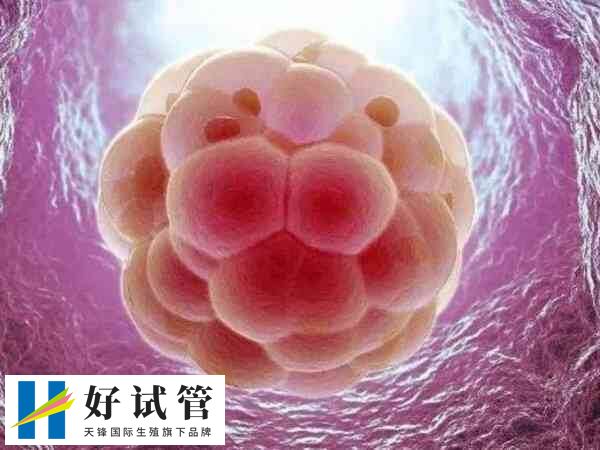

试管婴儿移植是指通过体外受精技术,在实验室中培养出受孕卵子后将其转移到女性子宫内,以实现人工受孕和生育的过程。一般移植胚胎有单个胚胎移植,或是多个胚胎移植,其区别有以下几点: